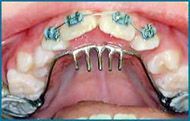

Other types of orthodontic appliances may also be used during the course of treatment. Some of these appliances are removable and can be taken in and out of the mouth, while others will be attached to the teeth until they are no longer needed.

Depending upon the specific needs of the case, these appliances may be used to accomplish a number of things including:

- Widening the jaws to make sufficient space for permanent teeth

- Influencing jaw growth

- The reduction of deep overbites

- Allowing the correction of teeth in crossbite

- Maintaining the space for a permanent tooth when a baby tooth has been prematurely lost

- Minor tooth movement

- Helping to control harmful oral habits